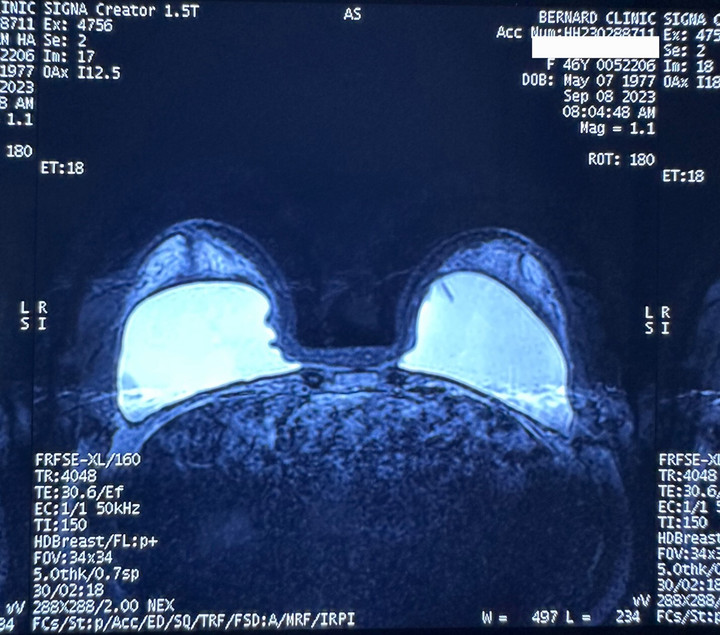

Ths.Bs Hồ Cao Vũ, đang công tác tại bệnh viện Chợ Rẫy cho biết thêm: “Ghi nhận trong hơn 200 ca tháo túi ngực trong 2023, thêm một nguyên nhân gây co thắt bao xơ thường thấy qua kết quả chụp MRI nhũ chuyên sâu do khoang đặt túi hẹp so với kích thước của túi ngực”.

Hình ảnh chụp MRI túi ngực bị gấp do khoang hẹp. (Ảnh:Ths.Bs Hồ Cao Vũ)

Ths.Bs Hồ Cao Vũ cho biết thêm, một trong những nguyên nhân ghi nhận trong các ca tháo túi ngực, vỡ túi bác sĩ nhận thấy khoang đặt túi hẹp so với kích thước túi. Túi ngực không được trải đều trong khoang, bị chèn ép bởi cơ, các mô sợi bên trong, theo thời gian nếp gấp vỏ túi tại các điểm bị ép lão hóa nhanh hơn gây nên nguyên nhân vỡ túi ngực sớm.

Tất cả các ca phẫu thuật nâng ngực đều được gây mê toàn thân, thuốc giãn cơ được sử dụng nhằm tạo thuận lợi cho quá trình phẫu thuật. Túi thường được đặt dưới cơ, giữa hai mặt phẳng (gọi là dual plane), trong phẫu thuật cơ được giãn hoàn toàn vì thế nếu tạo khoang vừa đủ với kích thước túi ngực, sau khi thoát mê cơ siết lại khoang sẽ hẹp so với kích thước túi khi bác sĩ không đủ kinh nghiệm để đánh giá.